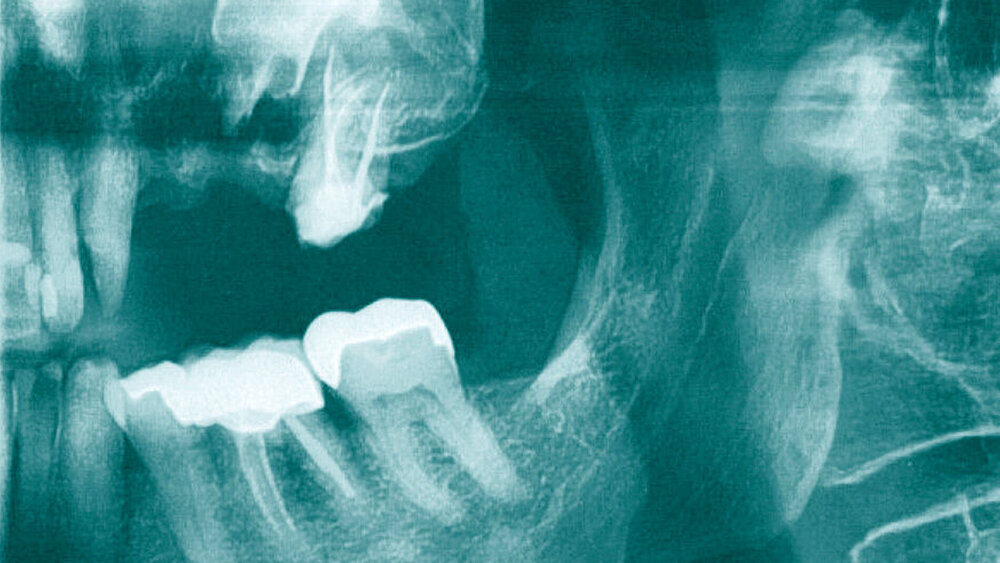

Intraoral lag ein unauffälliger Befund bei einem konservierend und prothetisch suffizient versorgten Gebiss vor. Von 23–27 befand sich eine provisorische prothetische Versorgung in Form eines Kunststoff-Brückenprovisoriums in situ. Es bestanden keine Schwellung oder weitere Entzündungszeichen im zweiten Quadranten. Aufgrund des röntgenologischen Befunds beim vom Patienten mitgebrachten Teil-Orthopantomogramm (OPT) (Abbildung 1) bestand der Verdacht auf einen in der linken Kieferhöhle lokalisierten Fremdkörper mit begleitender Sinusitis maxillaris als Ursache seiner Beschwerden. Zur genauen Lokalisierung des Fremdkörpers wurde als weitere Bildgebung eine Computertomografie der Nasennebenhöhlen (CT-NNH) durchgeführt. Die CT-NNH bestätigte den Verdacht auf Vorliegen eines Fremdkörpers innerhalb der Kieferhöhle sowie die nahezu vollständige Verlegung des Sinus maxillaris (Abbildung 2).